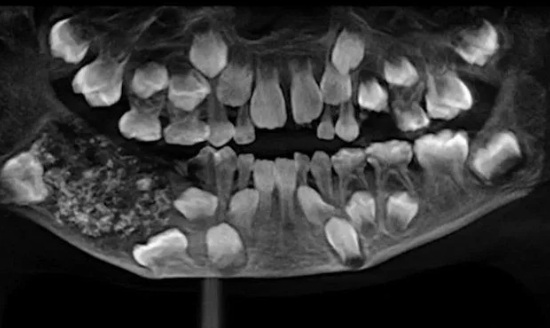

Esa hinchazón siguió creciendo hasta que finalmente el niño se sometió a una serie de estudios que indicaban la existencia de una estructura maciza de unos 200 gramos en el lado derecho de su mandíbula.

Una vez extraída en una intervención que duró hora y media, se descubrió que dentro de esa estructura había 526 piezas dentales de entre 1 y 15 milímetros.

Esta anomalía es conocida como odontoma compuesto, un tipo de tumor benigno relacionado con el desarrollo dental.

"La radiografía y la tomografía mostraron múltiples dientes rudimentarios en un tejido similar a una bolsa", sostuvo el doctor Senthilnathan, profesor del Departamento de Cirugía Oral y Maxilofacial de Saveetha, según citó el diario El Comercio de Perú.